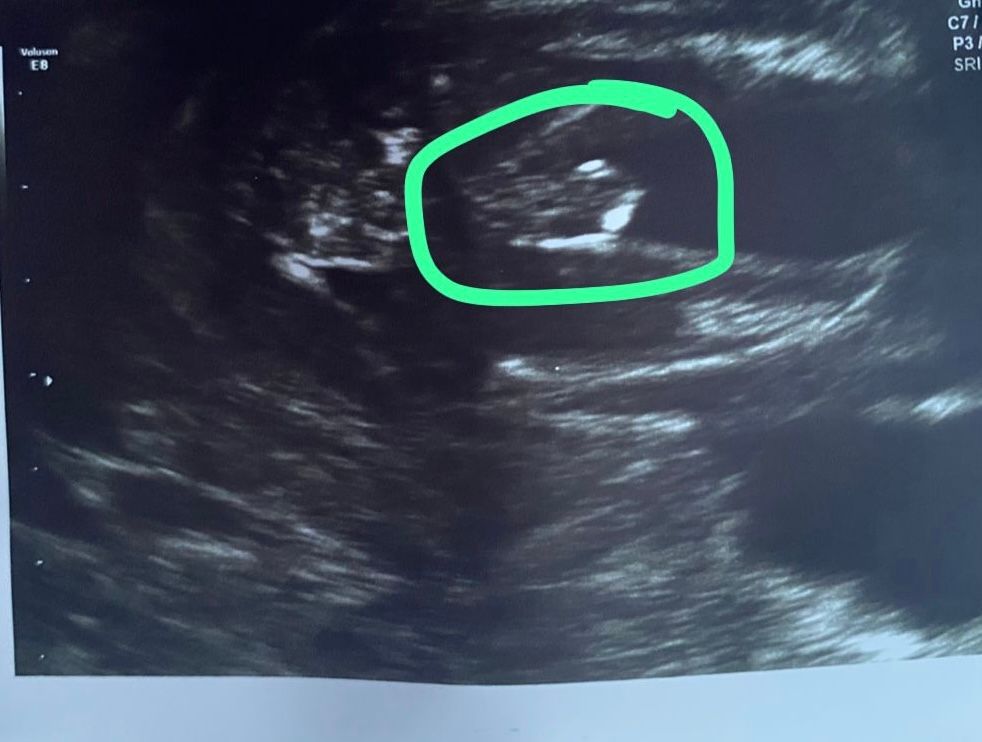

Как думаете, мальчик или девочка

Пол малышаДобрый день, сделала второй скрининг, пол попросила не говорить, но когда засняла видео с узи начала его разглядывать дабы найти пол )))

Теперь не могу понять, мальчик это или пуповина